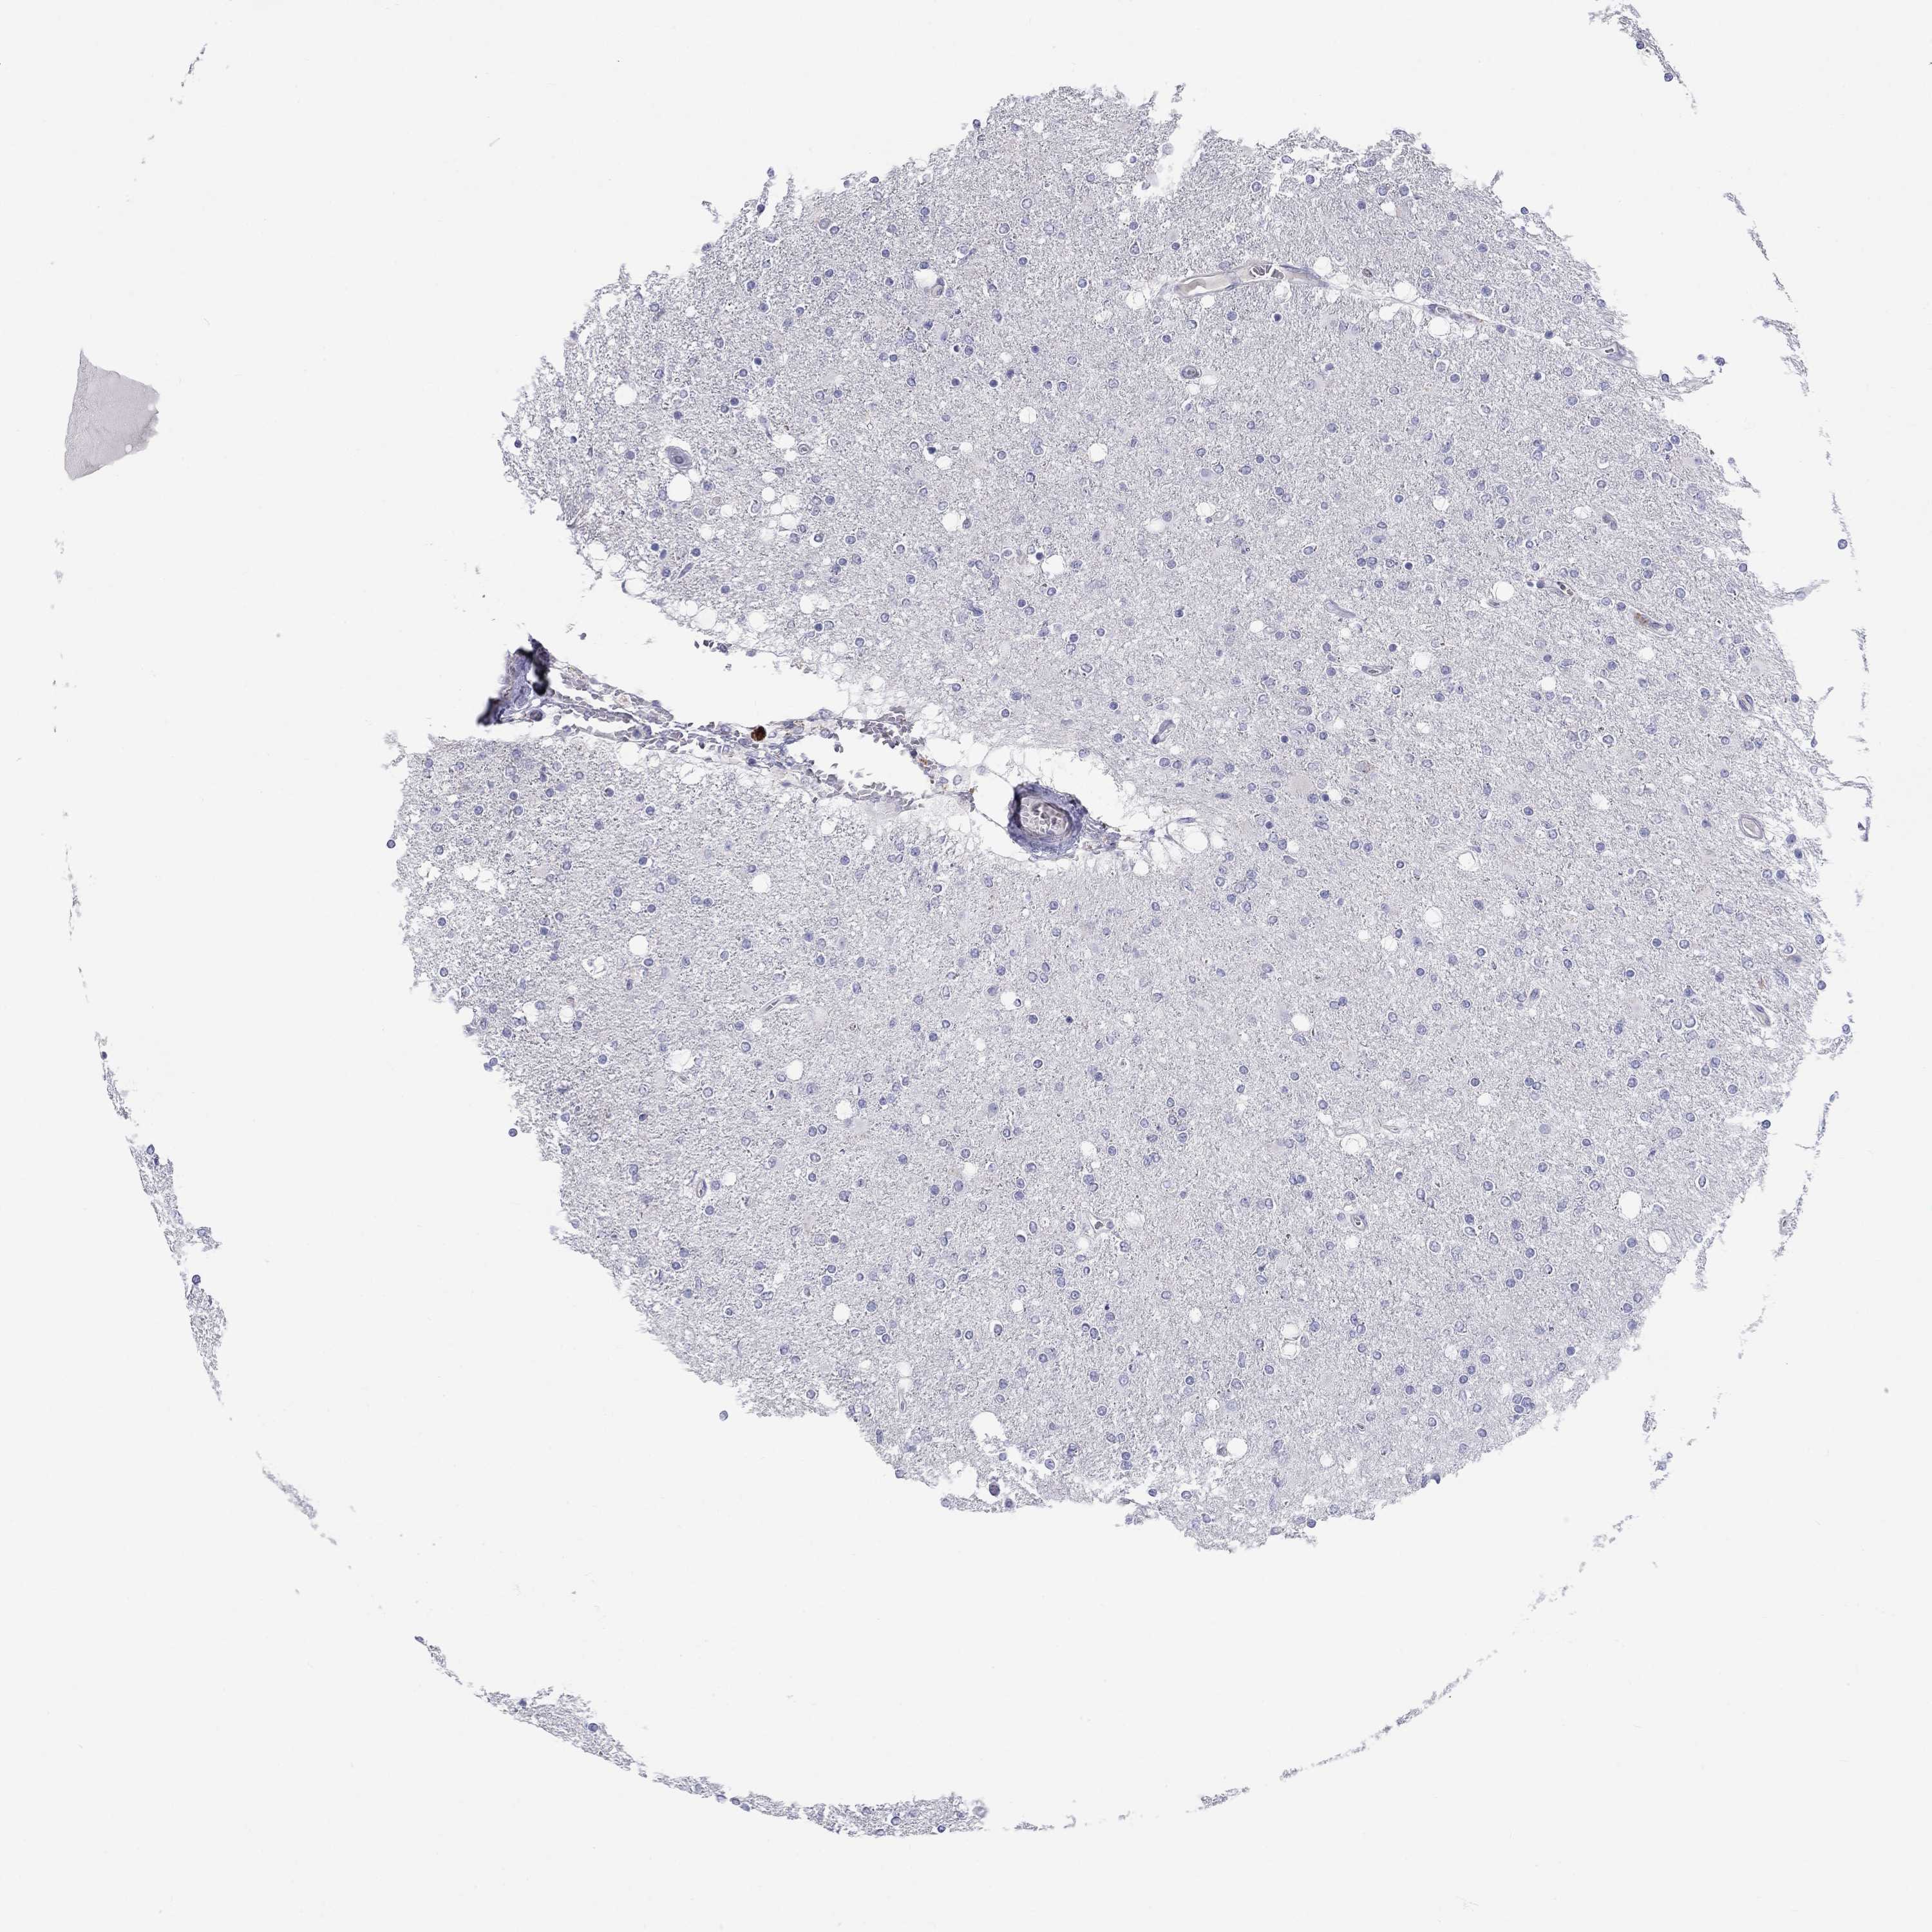

GLIOMA - Protein expressioni

A mouse-over function shows sample information and annotation data. Click on an image to view it in a full screen mode. Samples can be filtered based on level of antibody staining by selecting one or several of the following categories: high, medium, low and not detected. The assay and annotation is described here.

Note that samples used for immunohistochemistry by the Human Protein Atlas do not correspond to samples in the TCGA dataset.

Antibody stainingi

Antibody staining in the annotated cell types in the current human tissue is reported as not detected, low, medium, or high, based on conventional immunohistochemistry profiling in selected tissues. This score is based on the combination of the staining intensity and fraction of stained cells.

Each image is clickable and will lead to virtual microscopy that enables deeper exploration of all samples and also displays staining intensity scores, fraction scores and subcellular localization as well as patient and tissue information for each sample.

Antibody HPA068138

Antibody HPA071902

Staining

High

Medium

Low

Not detected

Intensity

Strong

Moderate

Weak

Negative

Quantity

>75%

75%-25%

<25%

None

Location

Nuclear

Cytoplasmic/membranous

Cytoplasmic/membranous,nuclear

Glioma, malignant, Low grade

Glioma, malignant, High grade

Glioma, malignant, NOS